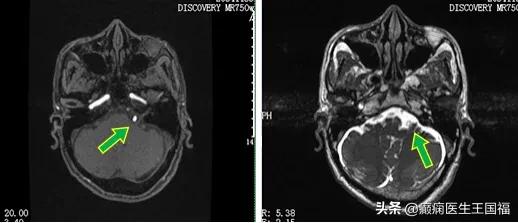

根据叶叔的MR颅神经扫描的影像资料,他的左侧椎动脉及其分支蜿蜒迂曲,压迫到了左侧面神经的根部,持续对面神经产生冲击。随着叶叔年事渐长,动脉逐渐硬化,这种冲击力越来越大,导致面肌抽搐越来越严重。

手术中证实,左侧的椎动脉就是压迫面神经的主要责任血管,手术中还发现,除了血管直接压迫面神经,这组神经血管之间还有很多蛛网膜粘连。即使用人工材料直接塞进神经和血管之间,粘连紧密的蛛网膜,也会将血管搏动的力量传导到神经上,术后复发、甚至手术无效的概率,会大大增加。